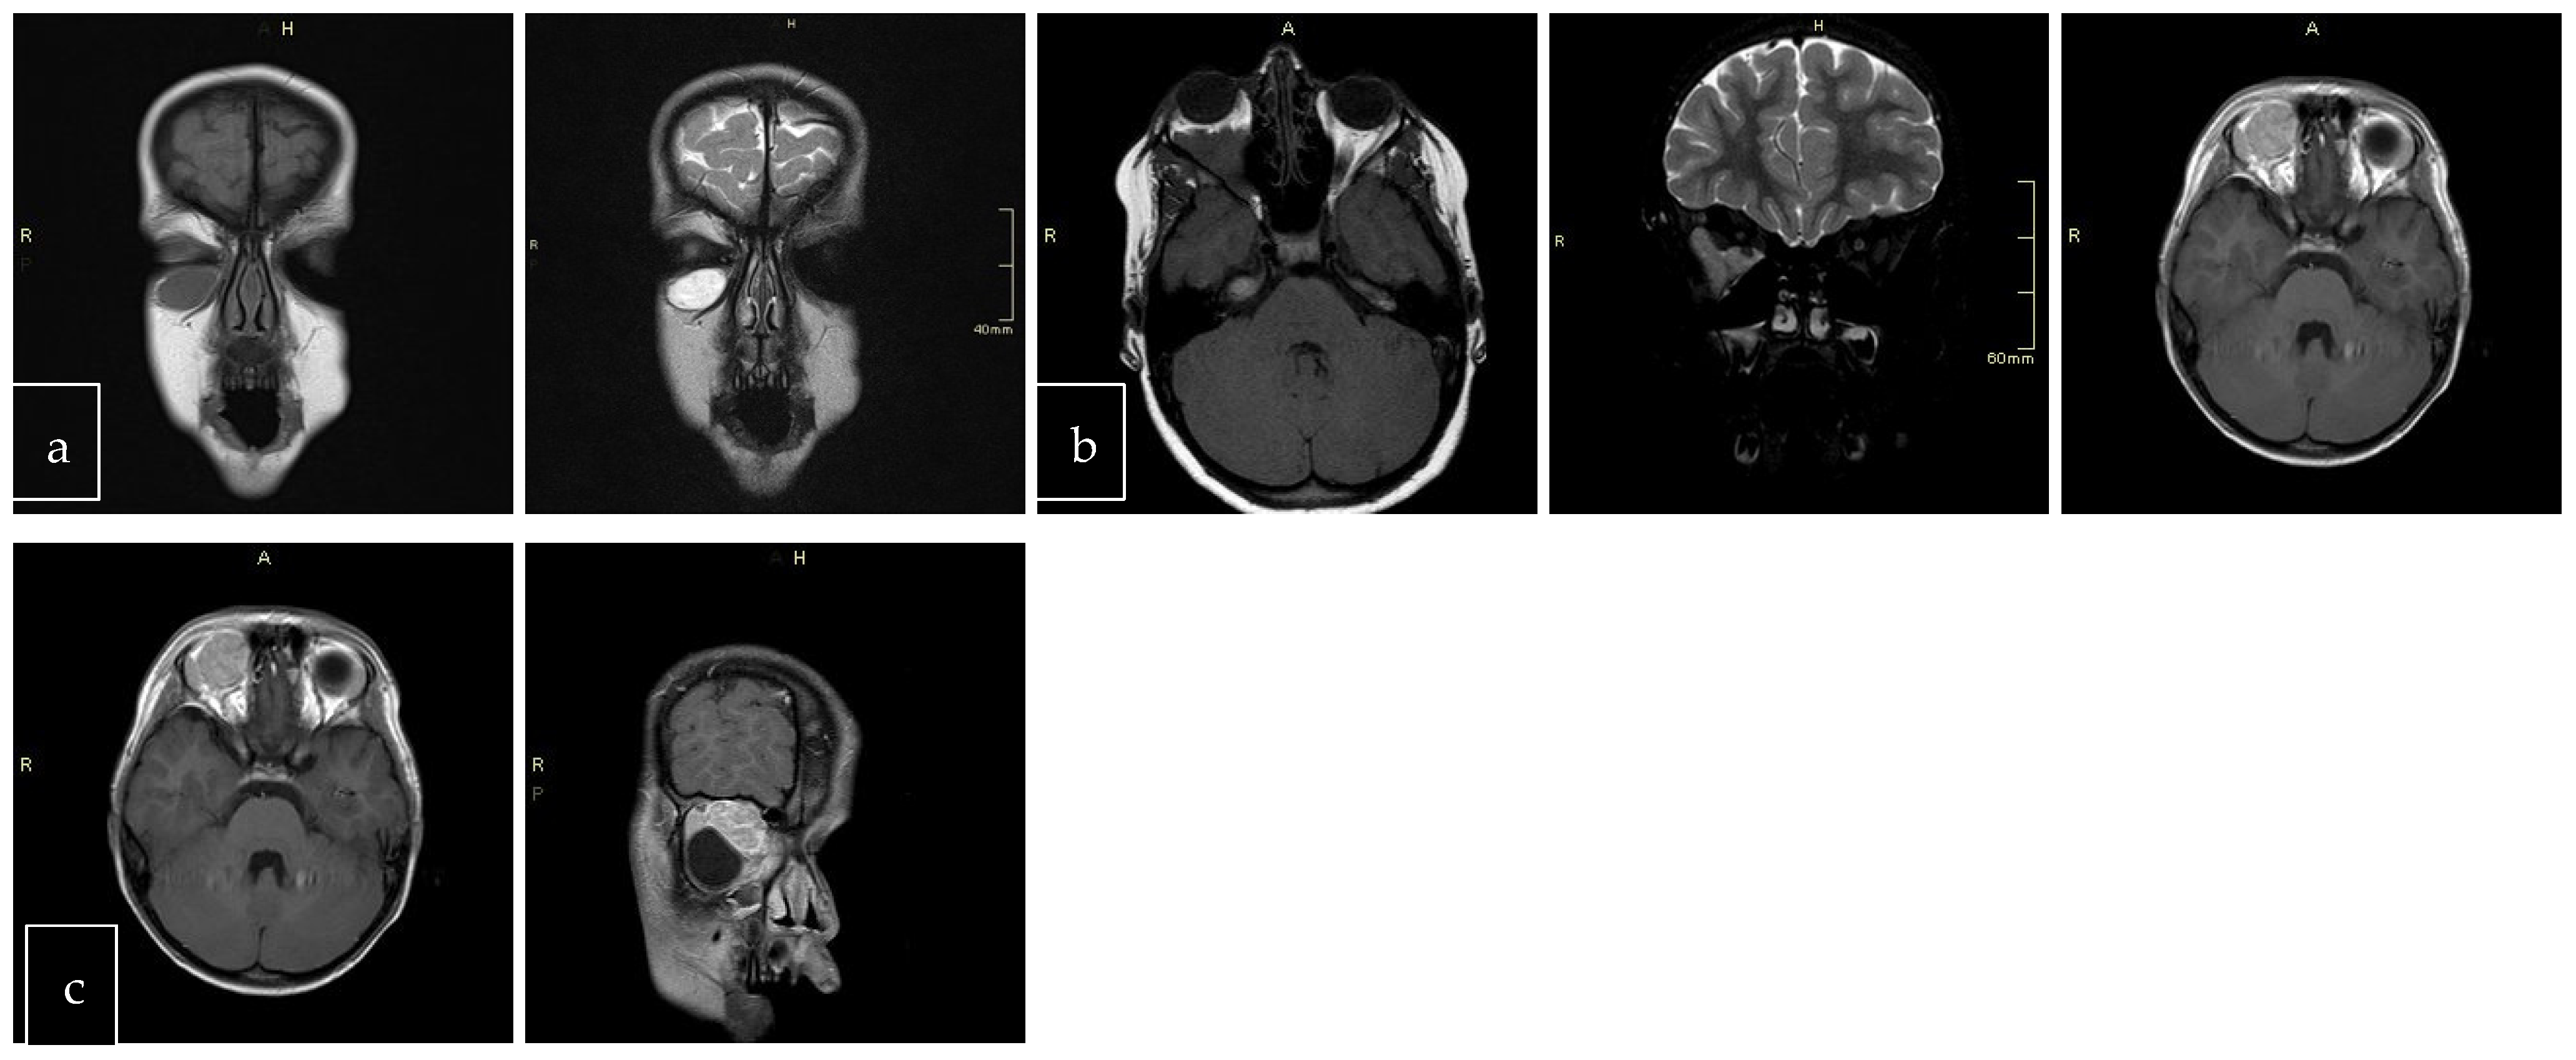

The scans at diagnosis showed masses with hypodense contrast enhancement of the tumor in all cases, with a pattern of generalized enhancement (see Figure 1). MRI at diagnosis showed low signal (isointense or hypointense) of soft tissues on T1-weighted images and high signal (hyperintense) on T2-weighted images, and gadolinium enhancement in all cases (see Figure 2). The tumor border was smooth (in 77% of cases), lobulated (10%), or mixed (13%) (see Figure 3). No association was found between tumor border type and recurrence rate or death.

Figure 3. Tumor border featuring (smooth, lobulated, mixed); T1 and T2 coronal sections of a smooth (a). T1 axial and T2 coronal sections of lobulated mass (b). T1 axial post-contrast sections of mixed border lesion with both smooth (axial) and lobulated (coronal) (c).